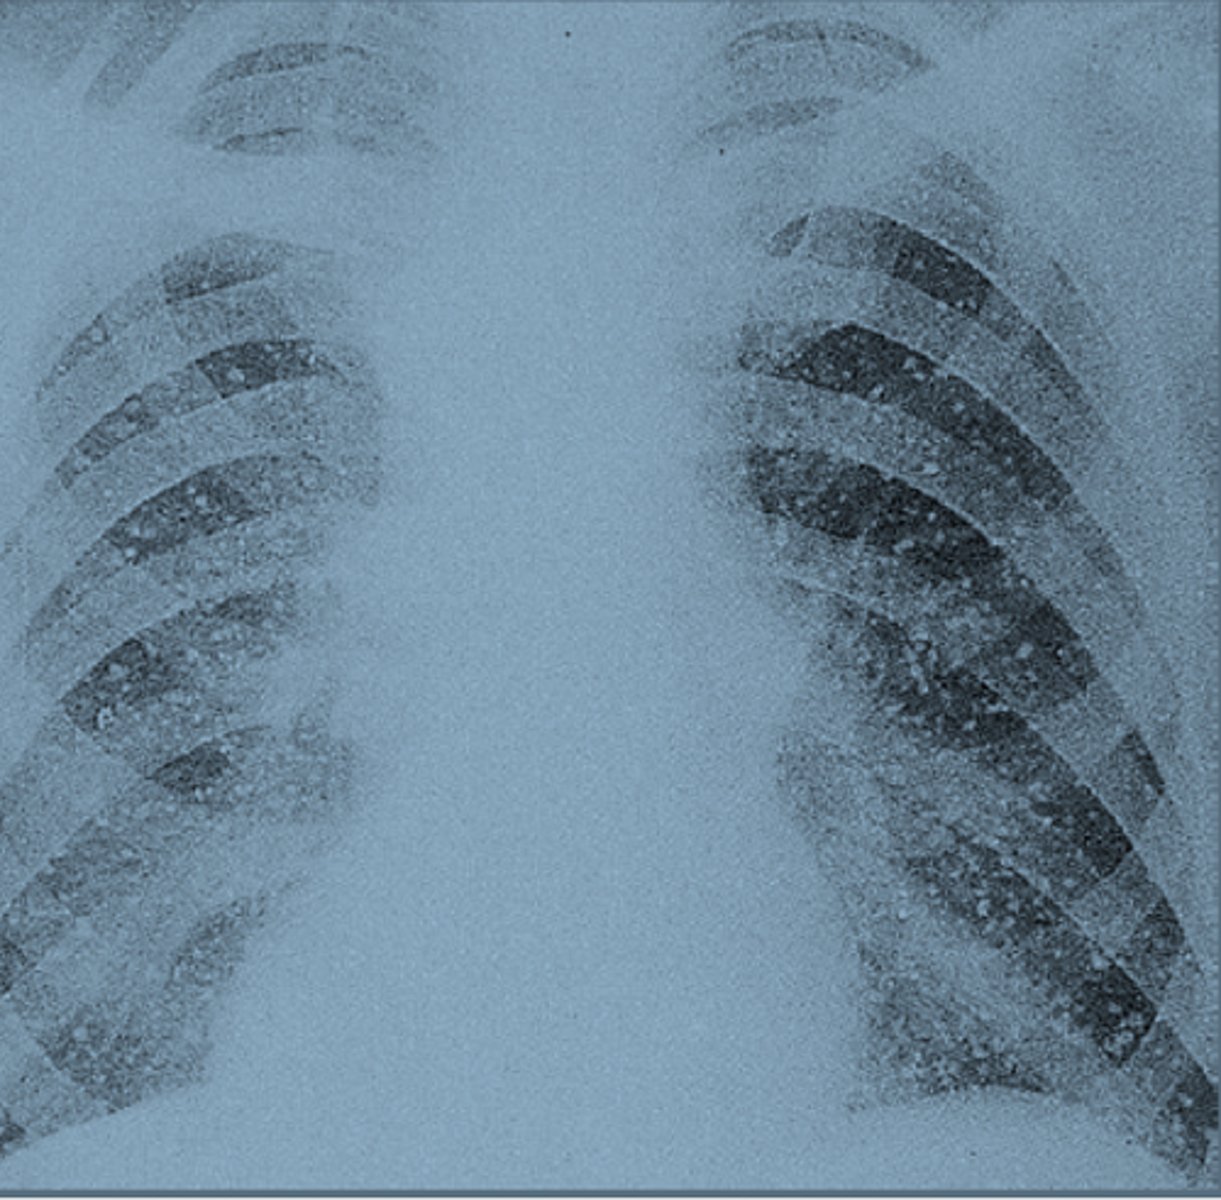

Histoplasmosis

a disease that results from the inhalation of an airborne fungus (often from bird or bat droppings) that can affect the lungs (usually presents as pneumonia) and may spread to other organs